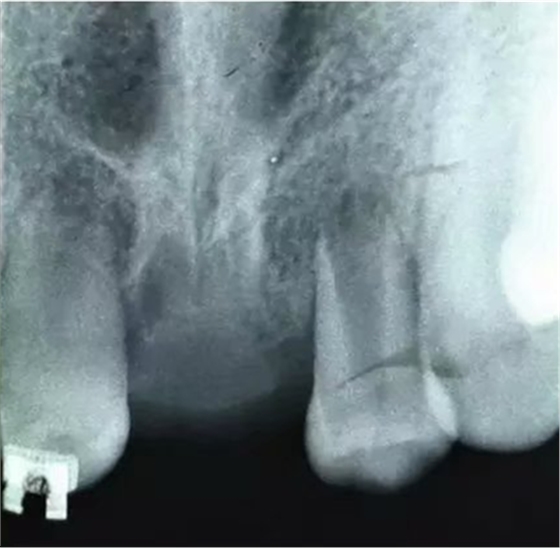

初步正畸牽引嵌入的上頜側(cè)切牙并重新獲得切牙空間。上頜側(cè)切牙的預(yù)后顯示有嚴(yán)重的牙根吸收。因此需要拔除上頜側(cè)切牙(圖3)。

【病例分享】上頜中切牙區(qū)外傷的自體移植和正畸治療

圖3. 影像學(xué)顯示上頜側(cè)切牙牙根吸收